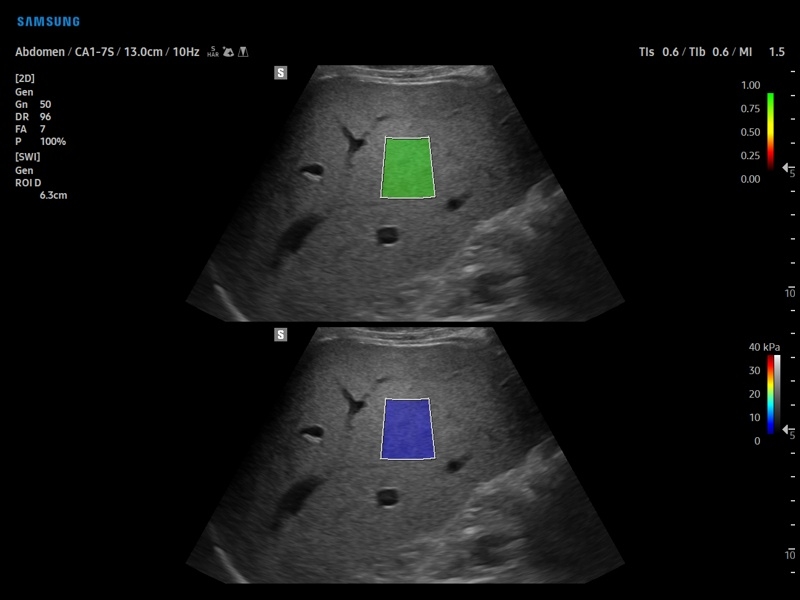

• S-Shearwave Imaging для эластографии сдвиговой волной

Эластография:

Компрессионная, Сдвиговая

Эластография сдвиговой волной/Эластометрия:

• Модуль S-Shearwave imaging – программа цветовой сдвиговой эластографии позволяющая автоматически определять индекс жесткости различных участков исследуемого объекта в кПа или м/с, получая при это еще и индекс достоверности данных RMI.